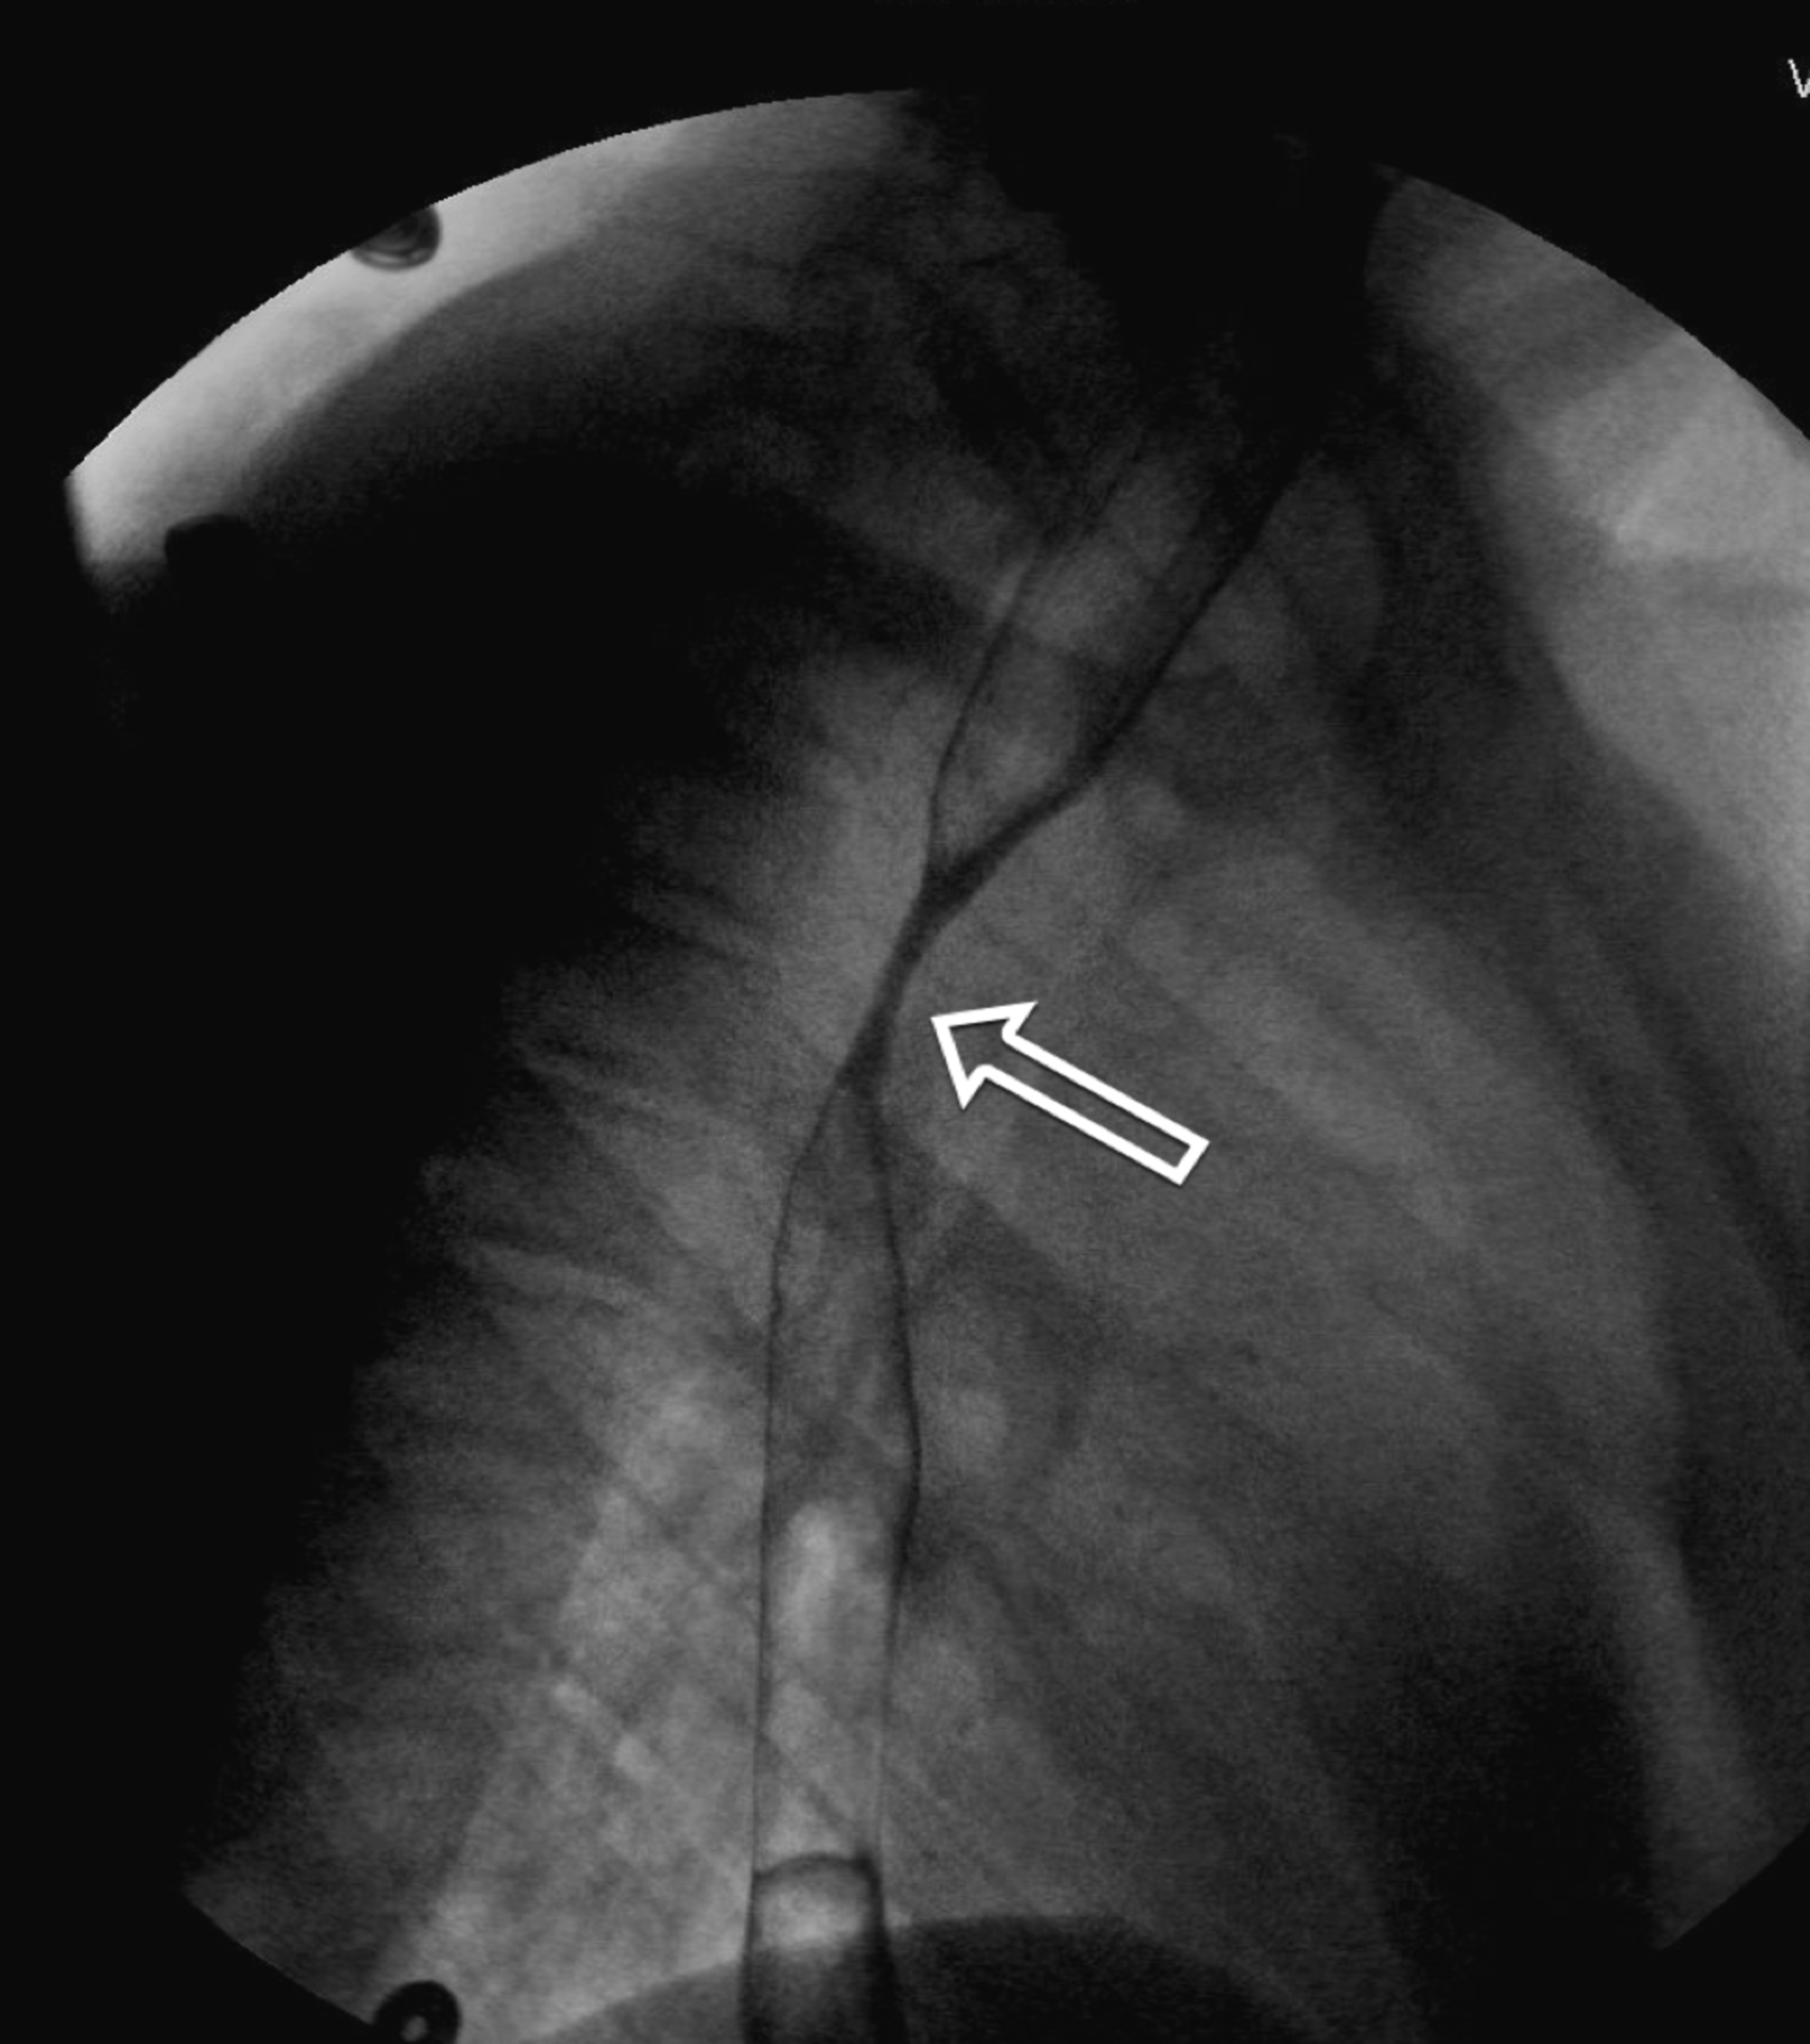

Diffuse Esophageal Spasm Corkscrew Esophagus The American Journal of

From www.amjmed.com

Diffuse Esophageal Spasm Corkscrew Esophagus The American Journal of Barrett's Esophagus Vomiting What are the symptoms of/what causes barrett’s esophagus? Barrett’s esophagus is a change in the cellular structure of your esophagus lining. The most common symptoms of gord. Although most people with barrett’s oesophagus don’t get cancer, the. It’s a risk factor for cancer, but the risk is low. Because barrett’s esophagus is often a complication of gerd,. Barrett's oesophagus is. Barrett's Esophagus Vomiting.